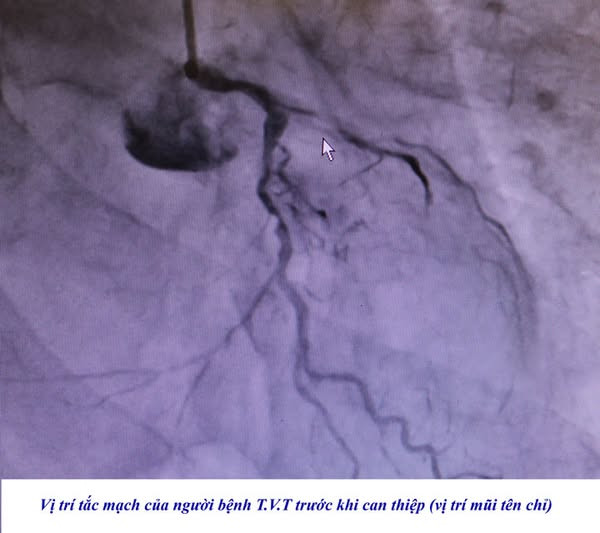

Nhập viện với triệu chứng đau tức ngực trái, đau dữ dội theo cơn, khó thở, 2 người bệnh được gia đình đưa đến cấp cứu tại Bệnh viện. Các bác sĩ nhận định cả 2 trường hợp đều có biểu hiện của nhồi máu cơ tim cấp nghi do hẹp tắc mạch vành cấp, ngay trong đêm các bác sĩ đã chỉ định chụp và can thiệp động mạch vành cấp cứu cho người bệnh....

| Hình ảnh tắc mạch vành trên phim chụp - Ảnh BVCC |